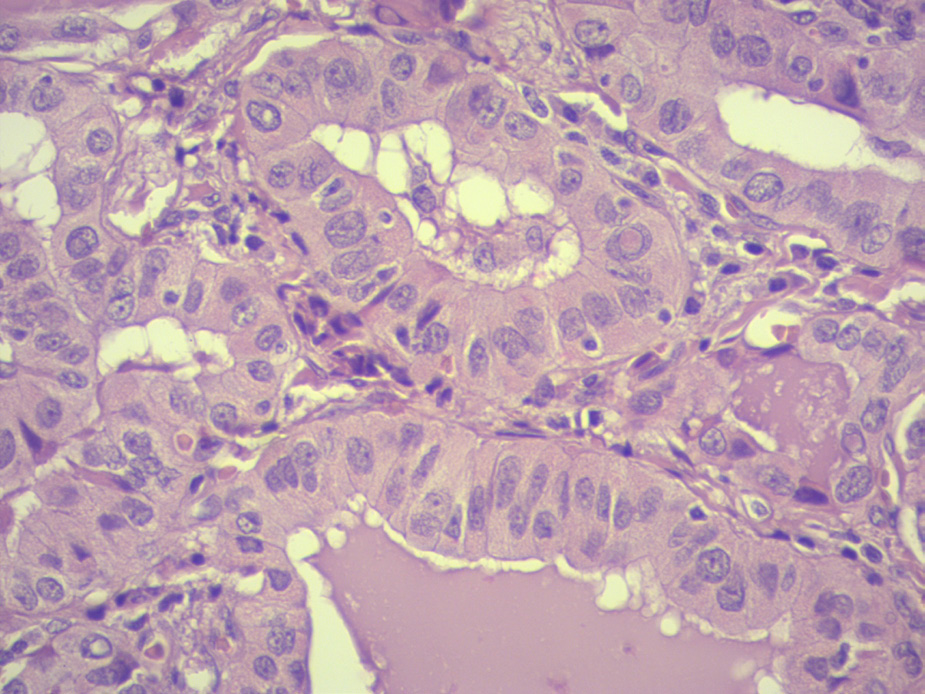

Caso 2: Mujer, 49 años, sin antecedentes patológicos a destacar. Ingresa por cuadro de tres meses de evolución por tumoración de cuello de crecimiento rápido, dolorosa, acompañada por disfonía, en eutiroidismo. Al examen se destaca: nódulo en lóbulo tiroideo derecho, de 4 cm, firme. Ecografía que mostró glándula tiroides aumentada a expensas del lóbulo derecho, con nódulo sólido, de 34x29 mm, heterogéneo, con sectores marcadamente hipoecogénicos y microcalcificaciones. Sin claro plano graso de separación del nódulo con músculos infrahioideos a derecha, pero si del paquete vascular. No adenomegalias cervicales. EUTIRADS5. PAAF Bethesda VI. De la valoración preoperatoria se destaca parálisis de cuerda vocal derecha, con buena luz glótica. Se realizó tiroidectomía total con vaciamiento central y lateral derecho. Del procedimiento quirúrgico se destaca presencia de invasión de músculos infrahioideos, recurrente derecho y músculo liso de esófago y faringe. La anatomía patológica informó carcinoma predominantemente papilar, compuesto en 60% por células de 3 a 4 veces mayor altura que ancho. (Figura 2) A nivel de la cápsula efracción capsular con invasión perineural; la lesión contacta con el margen cruento.

Figura 2: La figura muestra células tumorales tres veces más altas que anchas, con un citoplasma eosinófilo granular y presencia de pseudoinclusiones, características de esta neoplasia.

La incidencia global de cáncer de tiroides se encuentra en aumento. El carcinoma papilar generalmente sigue de curso clínico indolente, son una sobrevida a 5 años es del 98%. La variante de células altas representa el 1,3 al 12% de los CP, siendo la variante agresiva más común de los papilare carolinaguarneris. Posee un comportamiento agresivo, mostrando mayor incidencia de invasión extratiroidea (EET), linfovascular y metástasis a distancia, responsables de tasas de recurrencia más altas y peor pronóstico8. Desde el punto de vista histológico, se definen como tumores con estructura papilar revestida por células 2 o 3 veces más altas que anchas. Las células tumorales poseen abundante citoplasma eosinofílico. No existe consenso en cuanto al punto de corte de porcentaje de células de estas características que debe existir para ser catalogado como esta variante. Sin embargo, lo más aceptado es que el universo tumoral esté representado por más del 30-50% por células altas. Frecuentemente presentan evasión capsular. Múltiples trabajos describen la presencia de mayor compromiso ganglionar, EET e incluso metastásico (poco frecuente) en comparación del papilar clásico, lo que puede conferir un factor de riesgo independiente, con impacto en la evolución y sobrevida del paciente9. El compromiso del tracto aerodigestivo en el papilar es conocido hasta en el 7-16% de los casos. Los sitios incluyeron la endolaringe, tráquea, esófago, msculos infrahioideos y nervio laríngeo recurrente. Los patrones de invasión del tumor son comúnmente por extensión directa del tumor primario y menos comúnmente por extensión de ganglios linfáticos paratraqueales metastásicos10. El perfil molecular es variable, dentro de las mutaciones el papel fundamental es para el BRAFV600E con una prevalencia del 80% al 100%. Wong et.al.11 describen mayor frecuencia de mutaciones BRAF en casos con más del 50% de componente de células altas. Reordenamientos RET / PTC se han descrito en el 35,8% de los casos, en comparación al 17,2% del papilar clásico12.